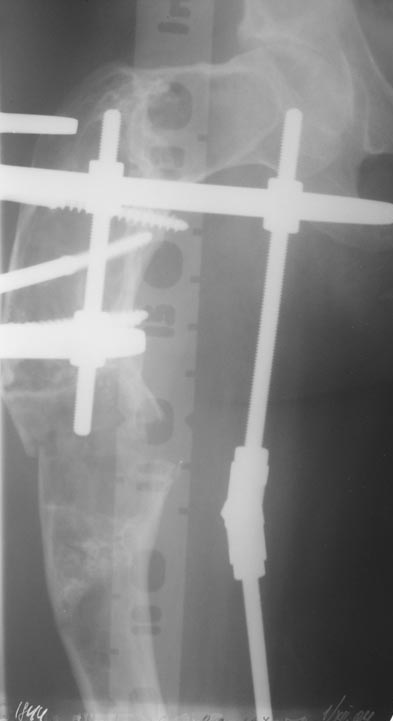

В ноябре этого года я обращался с просьбой о помощи в выборе тактики лечения больной с деформацией бедра на почве фиброзной дисплазии. Были получены интересные и очень полезные советы по операции.

Хотелось бы показать, что получилось в результате.

Операция выполнялась с помощью А.Н.Челнокова. Очень понравилась технология выполнения блокируемого остеосинтеза с использованием спицевого дистрактора, модифицированный гвоздь с латерализованным проксимальным отделом и возможностью многовинтовой фиксации проксимального и дистального участков бедра.